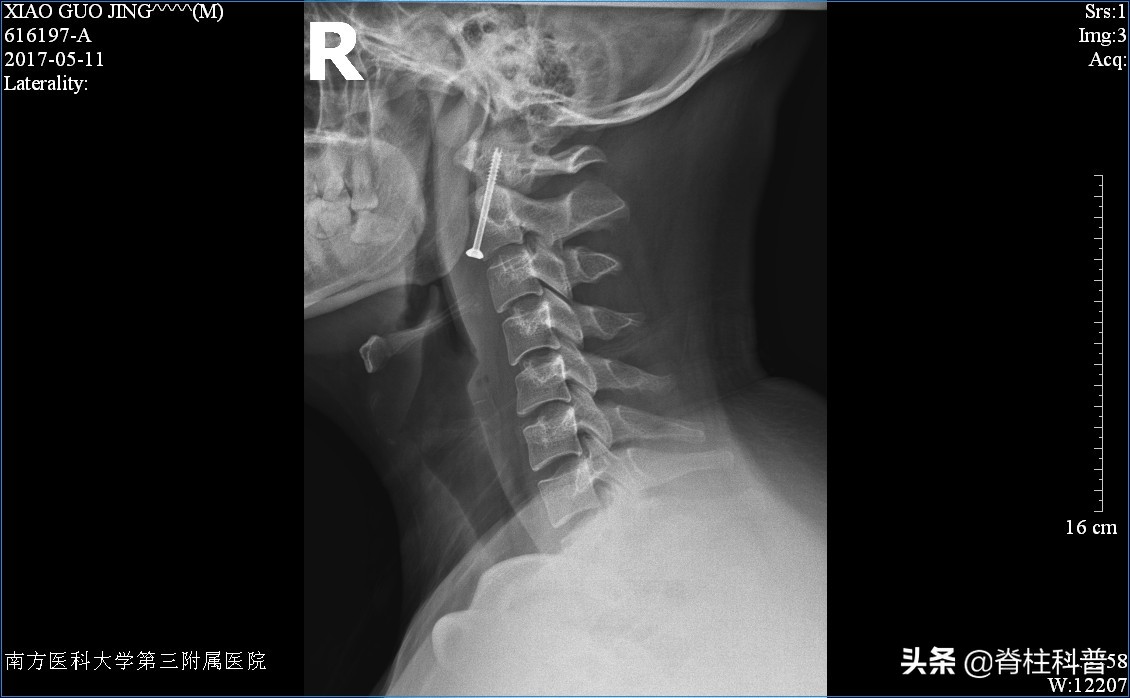

(颈前路枢椎齿状突骨折中空螺钉内固定术)

但这类的疾病的前路手术看似简单(打一颗钉子),实则因为解剖因素,手术风险大、技术难度高(高难度手术传输门:我们做了一台“自杀式”的手术 所有脊柱外科医生都不愿意做!)。而后路手术对颈部运动功能限制大。很庆幸,本次查房患者符合非手术治疗适应症。我们为他装上Halo-Vest架。

- 安装完毕后拍片检查复位情况,进行调整以达到理想复位。